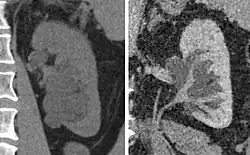

-

Peripelvic renal cysts may look like hydronephrosis on non-contrast CT (left image). However, CT urography (at right) reveals non-dilated calyces and pelvises.